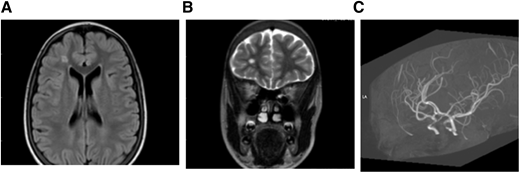

MRI (A) FLAIR (axial) and (B) T2W (coronal). Brain images from a 15-year-old female with SCA without neurologic complications according to history from parents and child. SCI seen in 2 planes measuring .3 mm in right frontal lobe deep white matter. (C) MRA: right and left cavernous ICA stenosis.

MRI (A) FLAIR (axial) and (B) T2W (coronal). Brain images from a 15-year-old female with SCA without neurologic complications according to history from parents and child. SCI seen in 2 planes measuring .3 mm in right frontal lobe deep white matter. (C) MRA: right and left cavernous ICA stenosis.